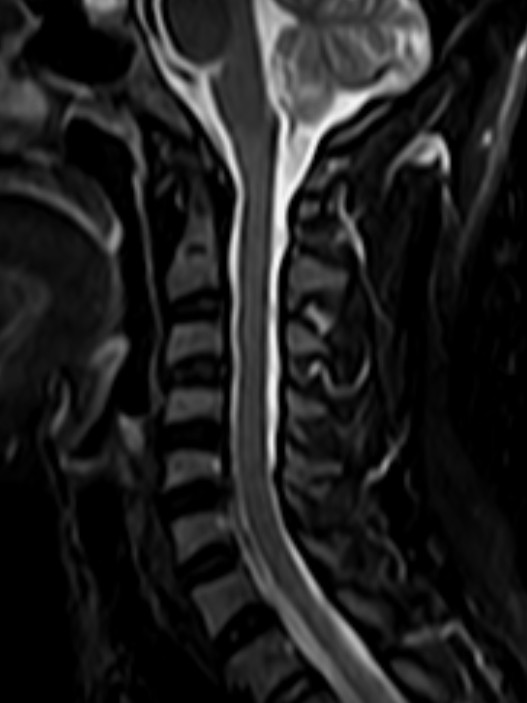

颈椎-STIR